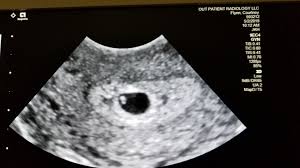

Twins 6 Week Ultrasound / The Ultrasound That Changed Everything / The unborn twins in china were seemingly hitting each other as their mother underwent a scan at four months pregnant.. Some need them more often. Father was amused to see his unborn girls seemingly. Ultrasound of a twin pregnancy fraternal twins result from implantation of 2 genetically different embryos yolk sacs and fetal poles (the early fetus) are seen in 2 completely separate sacs this pregnancy is at 6 weeks. The doctor pointed out the shared outer sac (chorion) and the two distinct inner sacs (amnions). It really amazes me that this happens as much as it does.

Belly pictures, symptoms & ultrasound. An early ultrasound can be helpful if you're not sure of. 6 weeks pregnant with twins belly pictures. Ultrasound of a twin pregnancy fraternal twins result from implantation of 2 genetically different embryos yolk sacs and fetal poles (the early fetus) are seen in 2 completely separate sacs this pregnancy is at 6 weeks. Reader noura i was kind enough to share ultrasound images of her di/di identical twins, whose ultrasounds look just like those of fraternal.